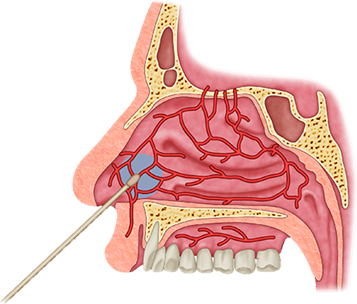

Cauterização

A cauterização nasal em consultório normalmente é indicada em pacientes com sangramento da região mais anterior do nariz quando recente e sem controle ou quando este torna-se muito recorrente. Nesses casos é utilizada uma substância como o nitrato de prata ou o ácido tricloroacético embebida em algodão que realiza uma cauterização química no local do sangramento. Esse procedimento normalmente é necessário nos sangramentos recorrentes da área de Kisselbach.